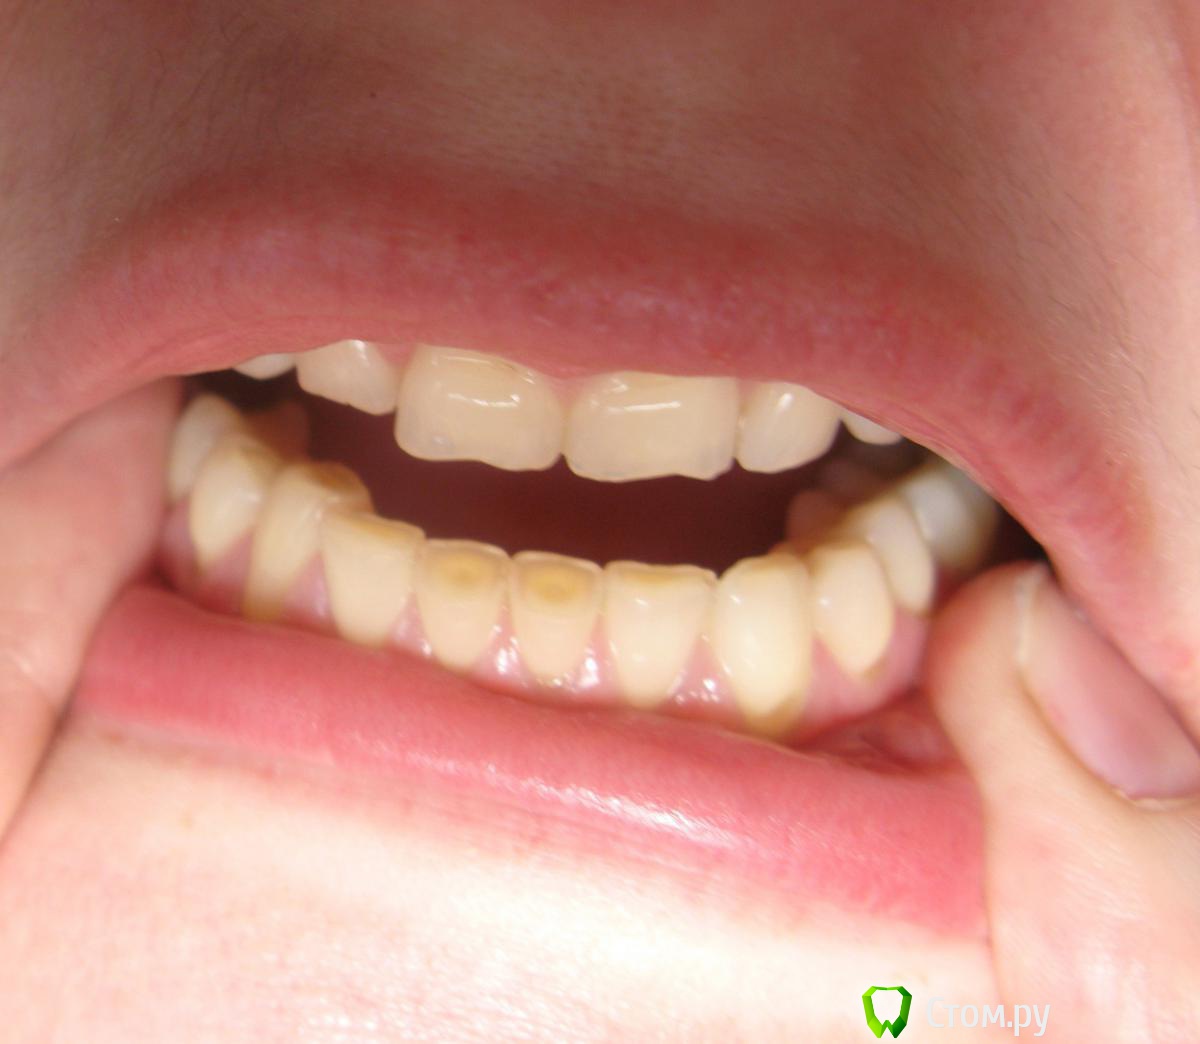

ylo99 Опубликовано 21 февраля, 2014 Поделиться Опубликовано 21 февраля, 2014 Здравствуйте ужаемые ортодонты!! очень нуждаюсь в помощи и в ваших советах.Мне 32 года. Живу в Москве.Прогрессирует стираемость нижних и верхних зубов ,(за последний год начали стераться и верхние зубы). Проблем с ВНЧС у меня нет, бруксизмом не страдаю. Нижняя челюсть недоразвита, ставила имплант в подбородок , чтобы как- то нормализовать профиль. Ассиметрия лица. Правый глаз расположен выше левого, а угол рта наоборот опущен вниз. Сами верхние зубы имеют наклон внутрь рта. Очень давно хочу решить эту проблему , но не знаю кого слушать . Сколько врачей столько и мнений. Одна сказала, вытягивать и верхние и нижние зубы. Другая- поднимать верхние вверх менять угол наклона . 3-я предожила насить каппу для постановки нижней челюсти в правильное положение , отправила к гнатологу, только потом брекеты. сегодня в цниисе, врач сказал, все зубы запротезировать у ортопеда -воостаносвить высоту, только потом брекеты.и челюстно лицевая операция . Мне нужен хороший специалист, которой за меня возьмется и до ведет дело до конца.Понятно что потребуется ортопед, но наверно после ношения брекетов. Уже не знаю к кому обращаться.Из снимков только ортопанограмма , 2 - летней давности. Ссылка на комментарий

Skip Опубликовано 4 марта, 2014 Поделиться Опубликовано 4 марта, 2014 У меня начались боли в шеи , голове, болит левый нижнечелюстной сустав . Куда бежать не знаю. Подскажите врача Ну вот, а говорили нет проблем с ВНЧС. Там, где Division II (резцы), всегда высокий риск развития дисфункции ВНЧС. Даже не знаю, кого Вам подсказать и куда бежать. Нижняя челюсть, действительно, короткая, но не смертельно. Хотя, учитывая симптоматику со стороны ВНЧС и ещё ряд проблем, всё это заставит доктора, который решится за Вас взяться, засучить рукава. Виртуально не могу сказать Вам ничего определённого, в отношении алгоритма лечения, т.к. для этого нужная непосредственная встреча, диагностика и пр. Предлагаемый Вам этап сплинт-терапии (капа, пишется с одним "П") будет неотъемлемой частью общего лечения, как собственно и полное протезирование в последующем. Ссылка на комментарий

Force Опубликовано 9 марта, 2014 Поделиться Опубликовано 9 марта, 2014 Лечение зависит от того, чего вы сами хотите. Каппа в терапевтическом положении позиционирует вашу нижнюю челюсть достаточно прилично вперед. Проблема в ретропозиции не только нижней, но и верхней челюстях. Вот и вопрос, чего вы сами хотите. Ссылка на комментарий